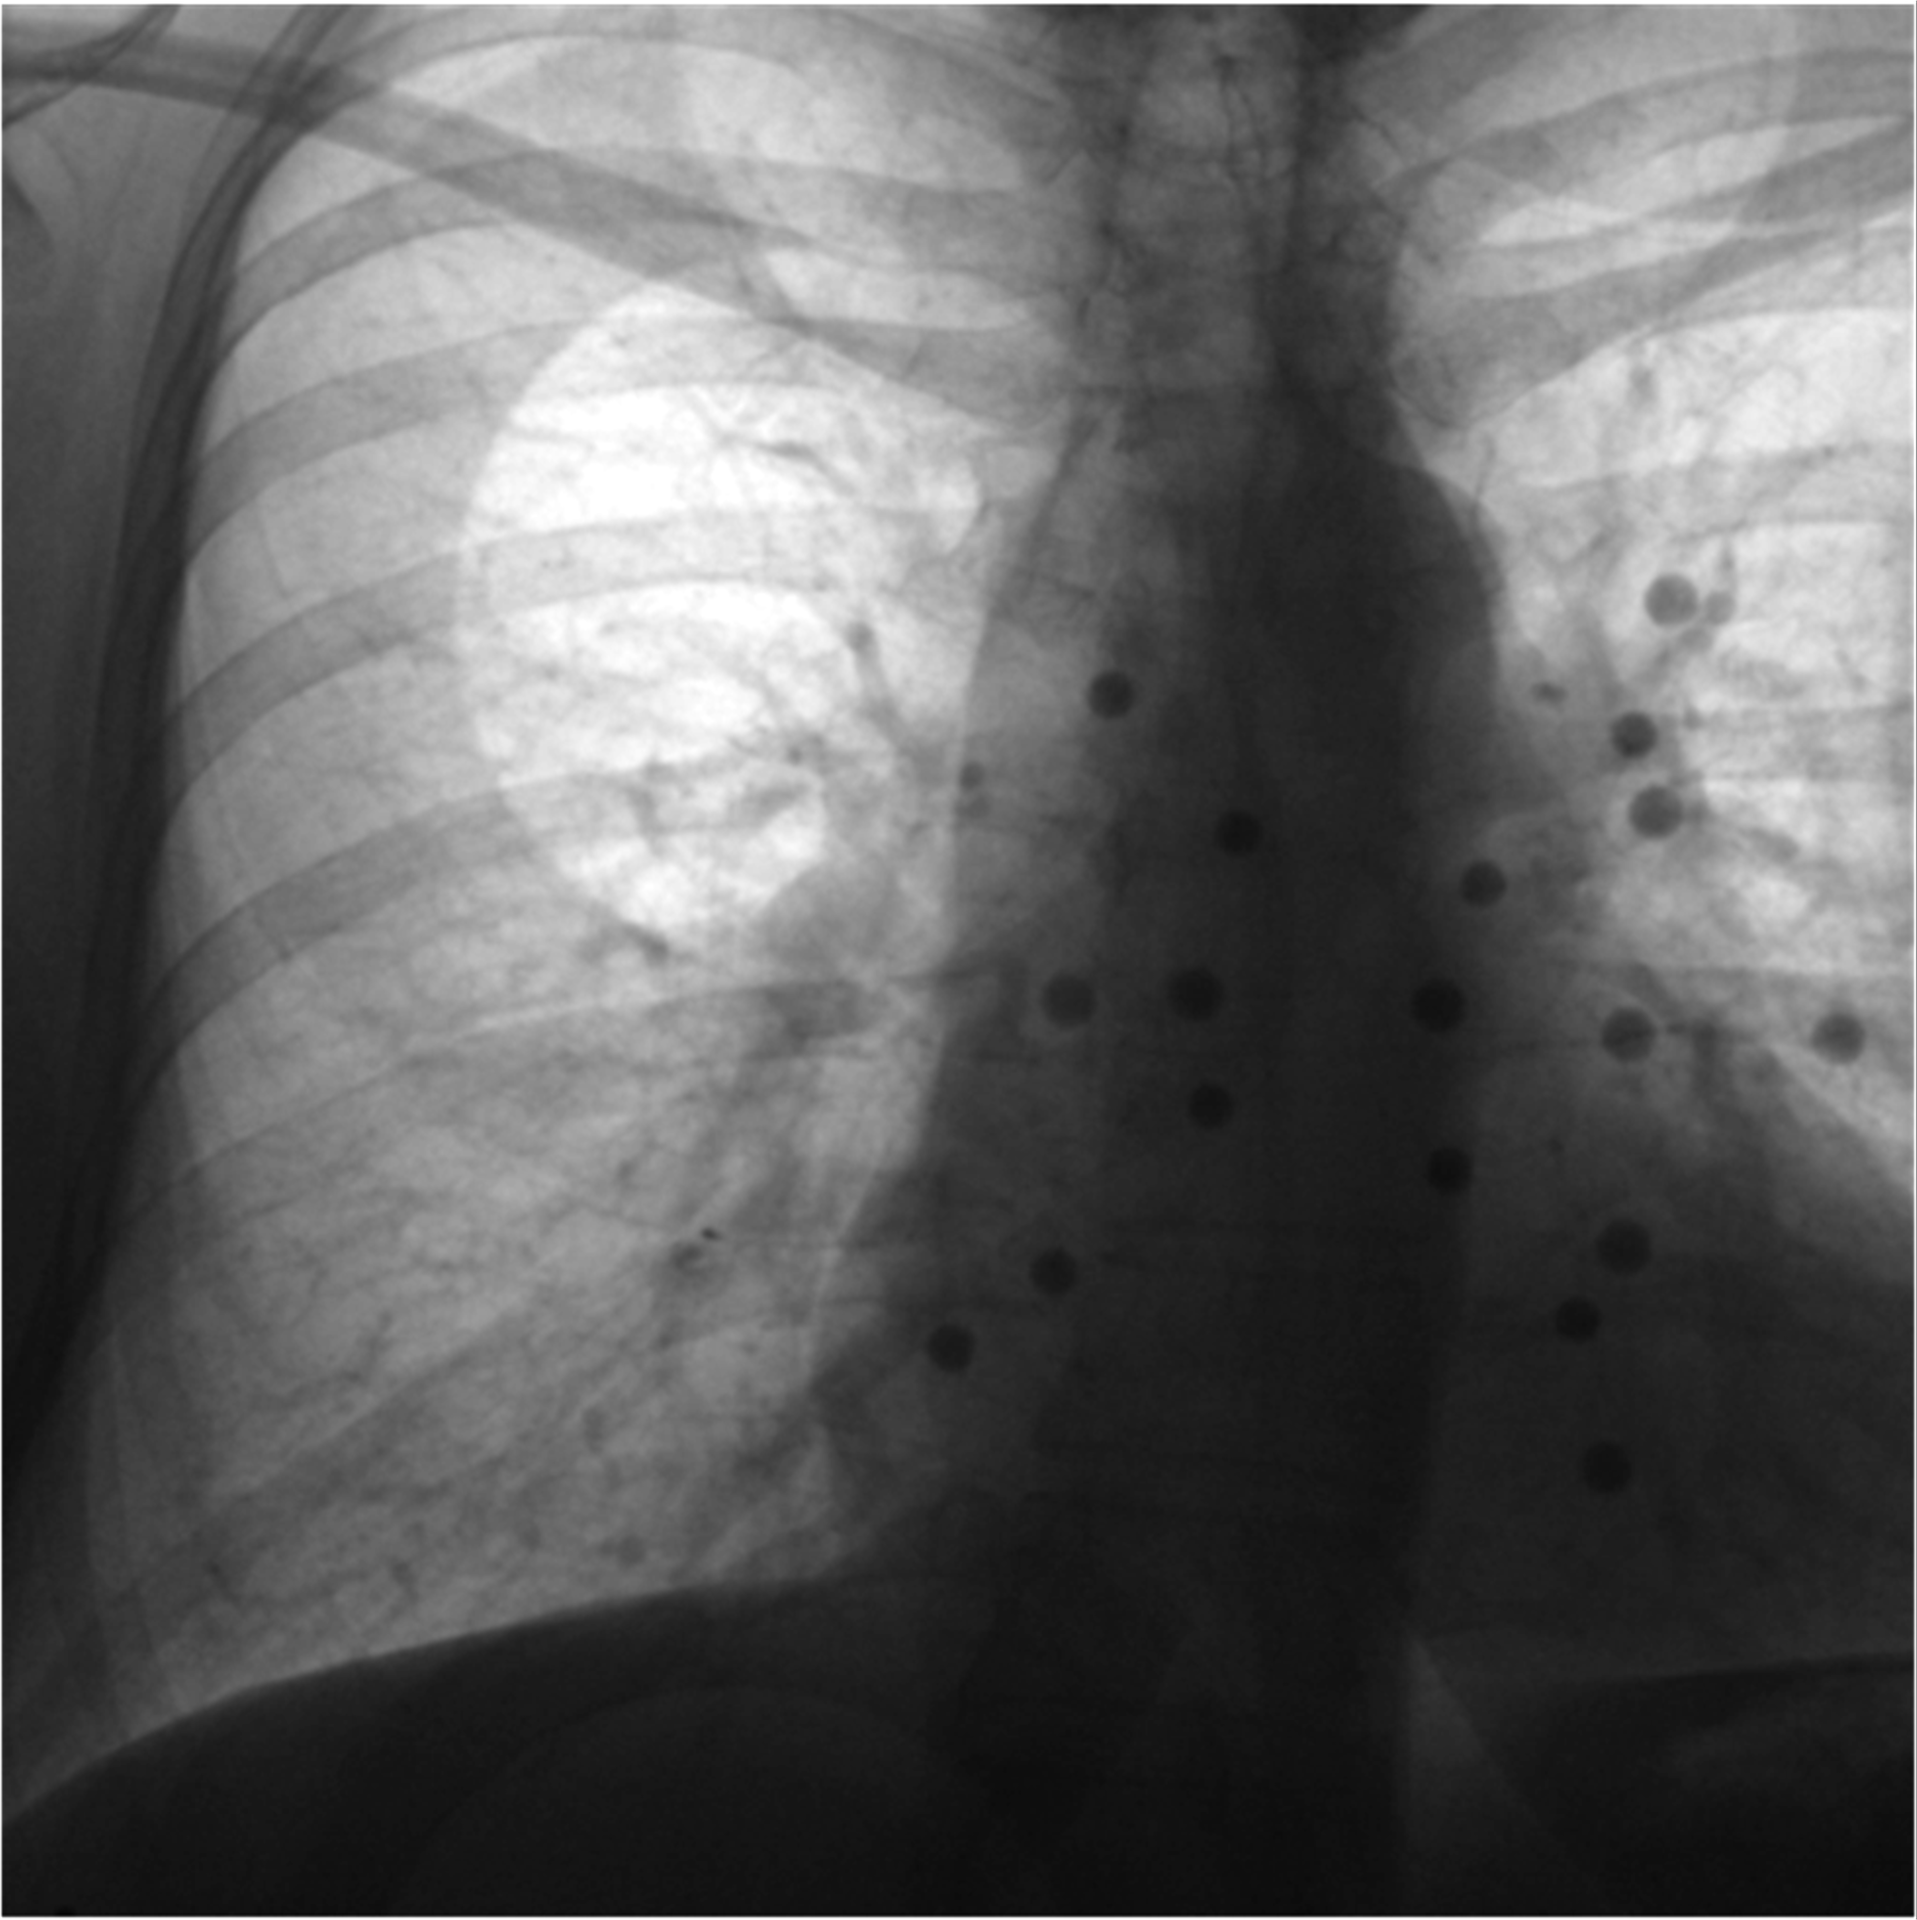

X-ray fluoroscopy continues to be the predominant modality for intra-operative image guidance, ubiquitously employed across various domains including cardiovascular, endovascular, orthopedic, and neuro-interventions, as well as in pain management and biopsies. The 2D projective nature of X-ray radiography presents significant limitations in fluoroscopy-guided interventions, particularly the loss of depth perception and prolonged radiation exposure. Integrating magnetic trackers into these workflows is promising; however, it remains challenging and under-explored in current research and practice. To address this, we employed a radiolucent magnetic field generator (FG) prototype as a foundational step towards seamless magnetic tracking (MT) integration, see Figures 1 and 2. Overall, we demonstrated the efficacy and clinical applicability of the MT-assisted approach. To the best of our knowledge, this is the first study to integrate a radiolucent FG into a fluoroscopy-guided workflow.

Figure 4 shows the setup of our FLUX-NAV system. The FG mounting frame is placed on the surgical bed without interrupting the clinical workflow.

Figure 4. FLUX-NAV system setup and coordinate frames for 2D and 3D navigation.